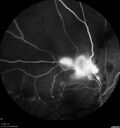

BRVO NVE Vitreous Hemorrhage Severe Non-Perfusion

50 year old man The right eye was fine and then there was a sudden change in the vision. When he is outside looking at something bright there are thousands of dots with squiggly lines through them.Â

PMHx: Type II DM (1 year), HTN, AnemiaÂ

VA OD: sc20/40 PH20/32 NscJ7

VA OS: sc20/160 PH20/25 NscJ2

IOP: TP: OD:16 OS:20

1+ NS OU